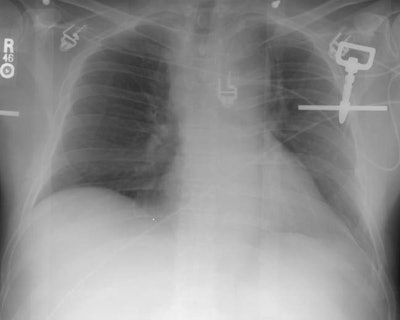

The frontal chest radiograph below was performed on a patient who presented to the emergency department following a 30 foot fall. The radiograph demonstrates widening of the mediastinum and an aortic contour abnormality with loss of the sharp outline of the aortic knob. Many of the other findings of aortic injury were not present and a CT of the chest was performed to evaluate for the presence of aortic injury (Click here to view the CT scan and arteriogram).